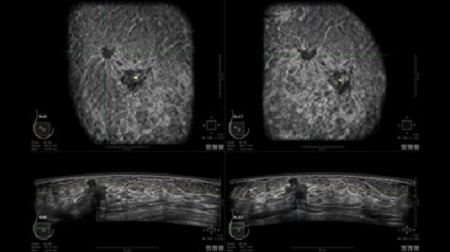

GE INVENIA ABUS – это современный УЗИ аппарат, который создан для точной и эффективной диагностики сканирования с высокой плотностью молочных желез. Выявляемость патологий раковых и предраковых стадий заболевания составляет 55%, что в конечном счете позволяет ставить врачу точные и своевременные диагнозы. Традиционные методы использования маммографии не показывают такой выявляемости, ограничиваясь лишь 3-38%.

УЗИ-аппарат GE INVENIA ABUS позволяет проводить максимально операторонезависимые процедуры, что значительно снижает риск неправильной постановки диагноза и сопутствующие издержки на обработку информации. Система готовит отчет в течение 3-х минут после сканирования, это безусловное преимущество по сравнению с обычным УЗИ сканером.

• сканирование одной грудной железы в трех проекциях не более 60 сек.;

• Получение объемных 3D изображений с возможностью покадрового просмотра

• Отображение объемных 3D ультразвуковых изображений, которые состоят из традиционных поперечных и воссозданных коронарных и сагиттальных проекций

• Многооконный просмотр: 4 - 12 изображений

• Стандартизованная ориентация изображения: «толстый срез» в коронарной плоскости; поперечная; сагиттальная плоскость; радиальный и антирадиальный поворот изображения; просмотр исключительно области интереса

• Одновременный просмотр двух изображений для сопоставления в коронарной плоскости